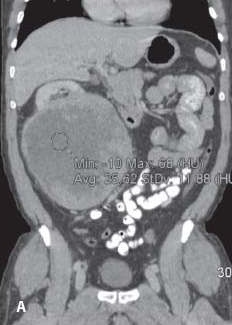

The results of the study comparing Aveo’s tivozanib to sorafenib for the treatment of metastatic renal cell carcinoma showed no improvement in overall survival, the basis for the FDA’s rejection of the company’s new drug application earlier this year.